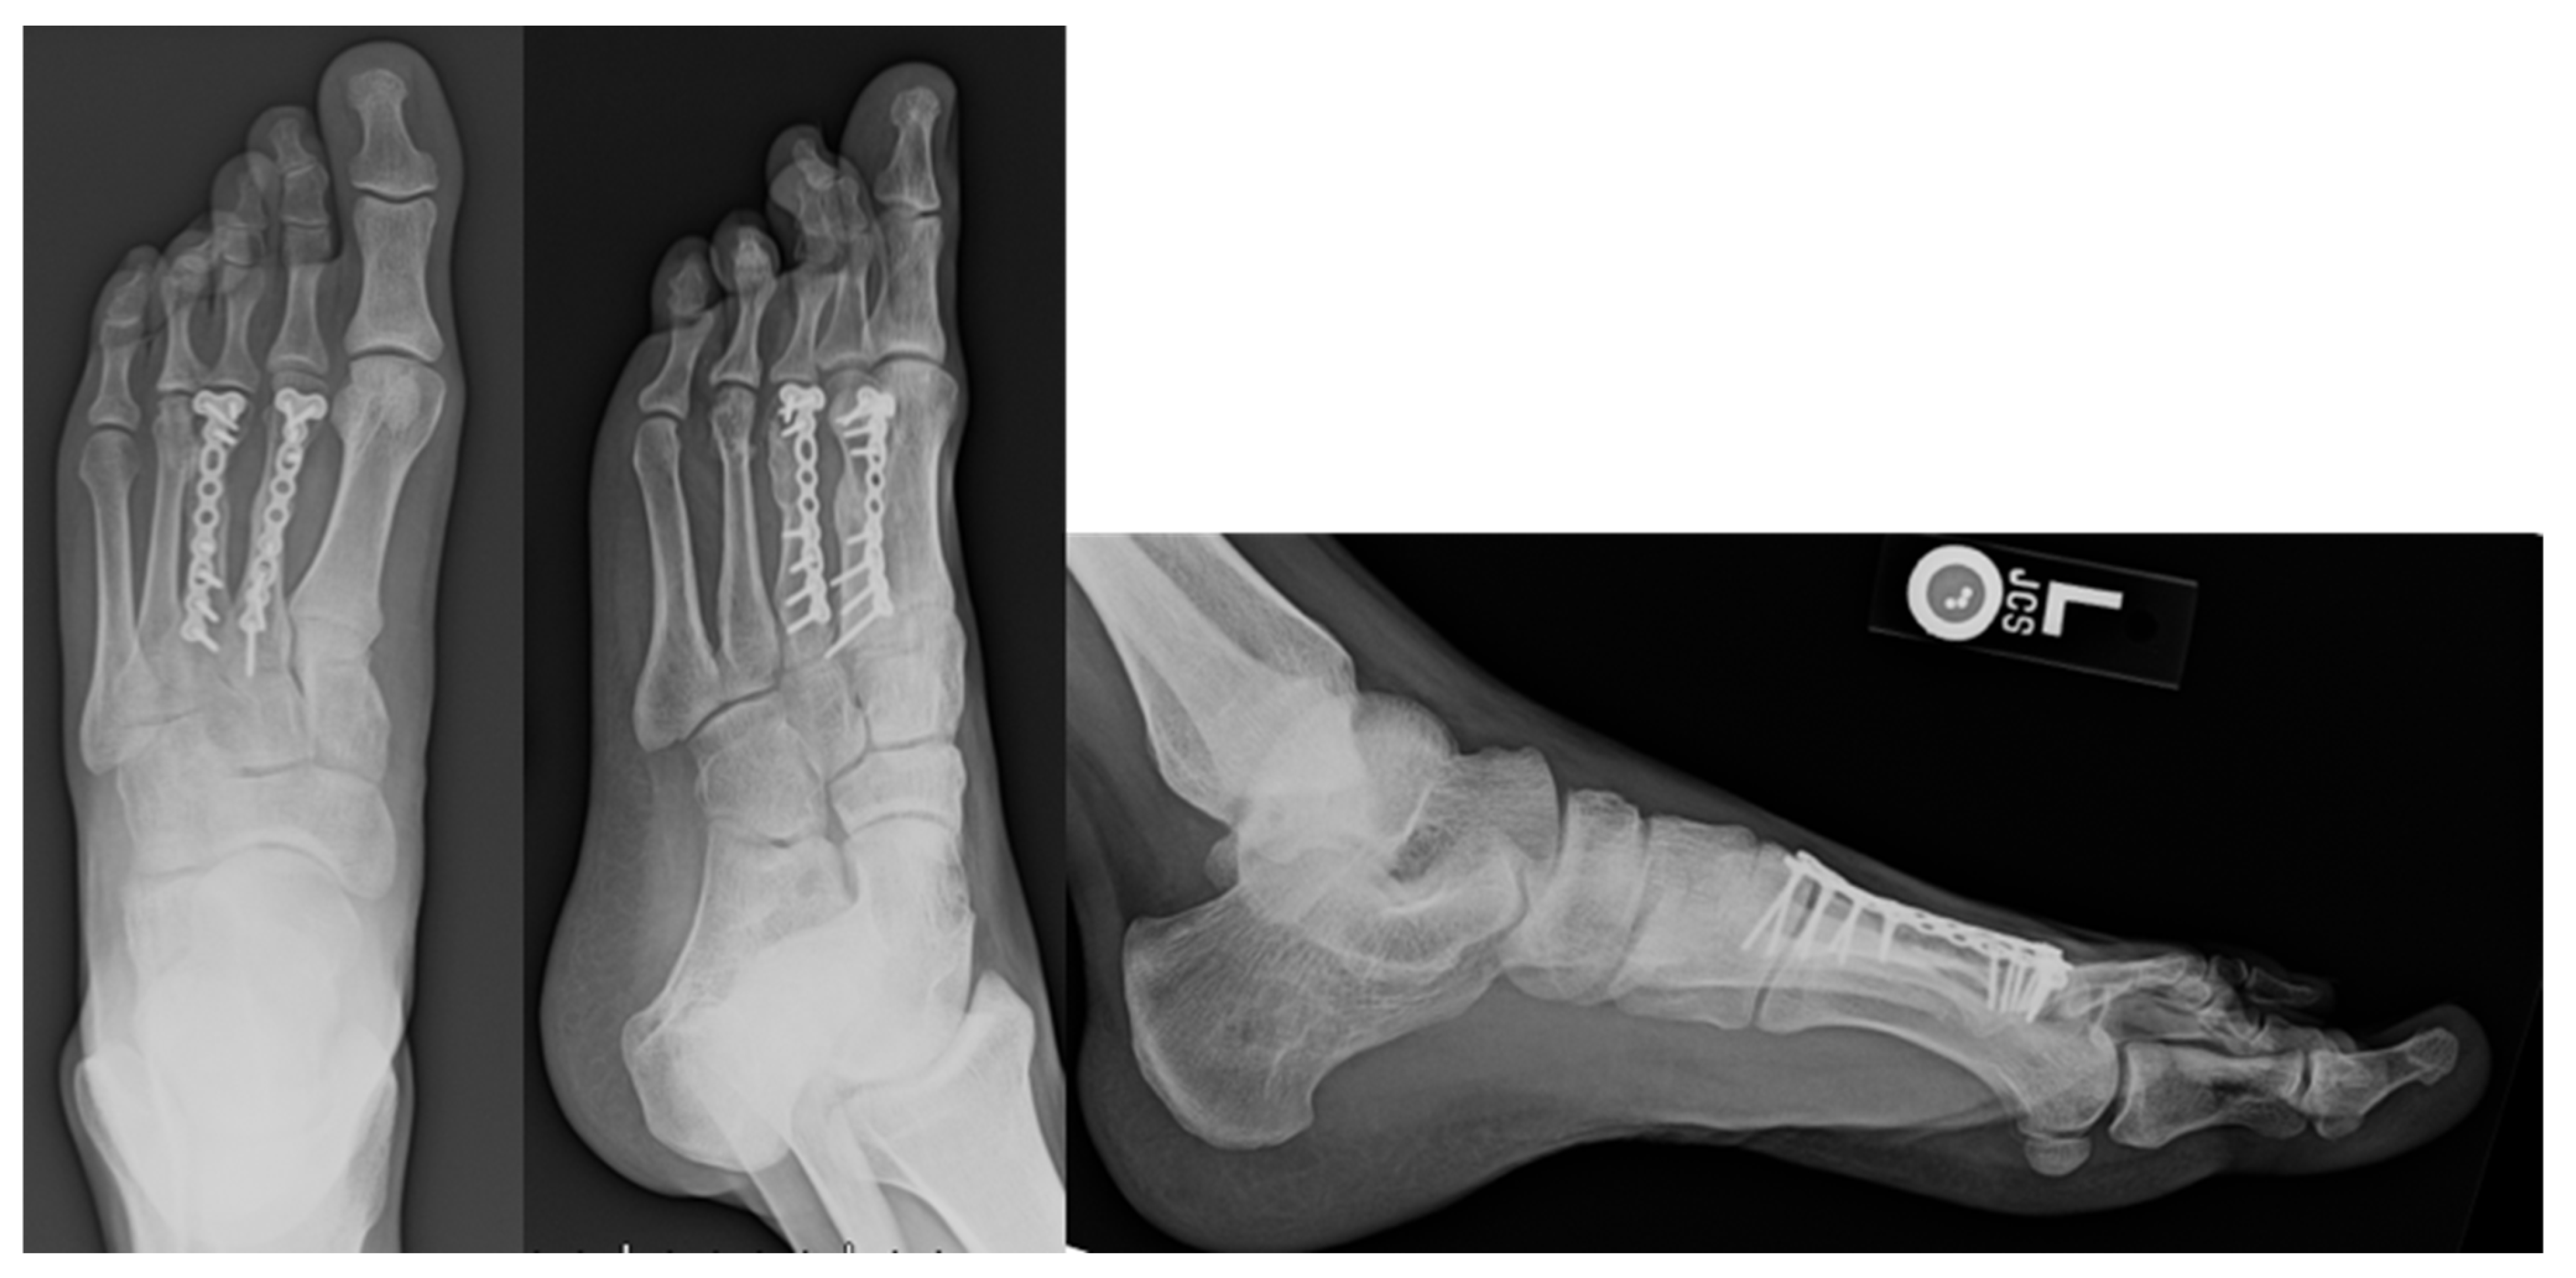

Figure 2.

Post-operative Images for Displaced Non-union. Displayed above are the radiographs for second and third metatarsal fractures following a gunshot injury that underwent ORIF due to a non-union.